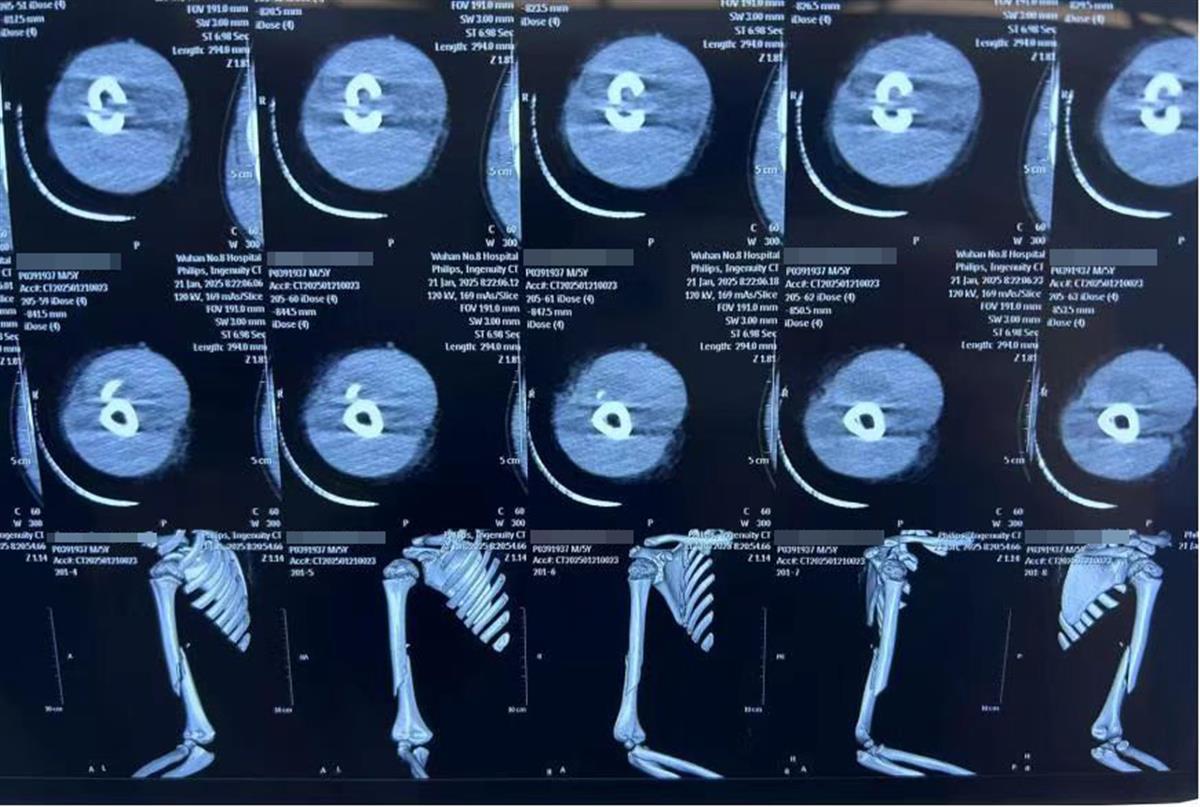

术前CT可见右肱骨骨折

经过术前评估,创伤外科团队为乐乐制定了手术方案,并在麻醉科、手术室的配合下,将两根髓内针预弯成C型和S型,精准定位后固定骨折端。手术不到1小时,乐乐出血量极少。术后X光片显示,骨折端对位良好。